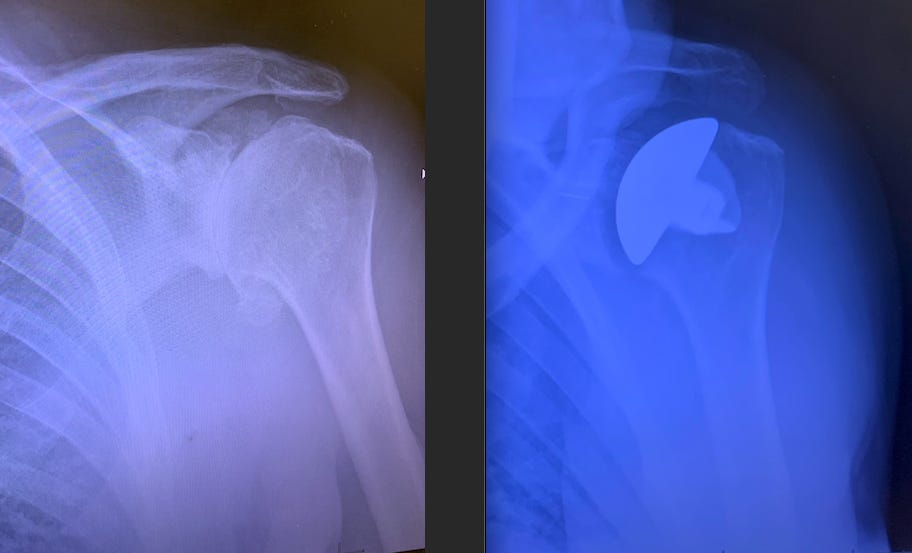

The left x-ray shows “bone-on-bone” with extra growth around the joint. This is osteoarthritis, which is degeneration due to wear and tear. I did too much liposuction,* weightlifting, and rock climbing.

The image on the right shows the new steel humeral head and a darker area between it and the original socket. This is plastic. The extra bone has been nipped out.

If you have the right doc, total shoulders are fantastic. My surgeon, Kaiser’s Daniel Acevedo, has performed over 1000, and he invented and published about some parts of the procedure. My surgery took him only an hour. I required Advil nearly every day for the past three years, but now, six weeks post-op, I am pain-free. Fast and accurate surgeries lead to easy recoveries and less chance of complications because there is less tissue damage.

I’m not exactly a bionic man—shoulder implants wear out 15 to 30 years after the surgery. Younger patients who get these replacements may eventually need a second procedure, which is more complex. But since I’m 68, I don’t worry much about that. I have friends who are climbing with two fake shoulders six months after getting their last one, and I intend to try as well.